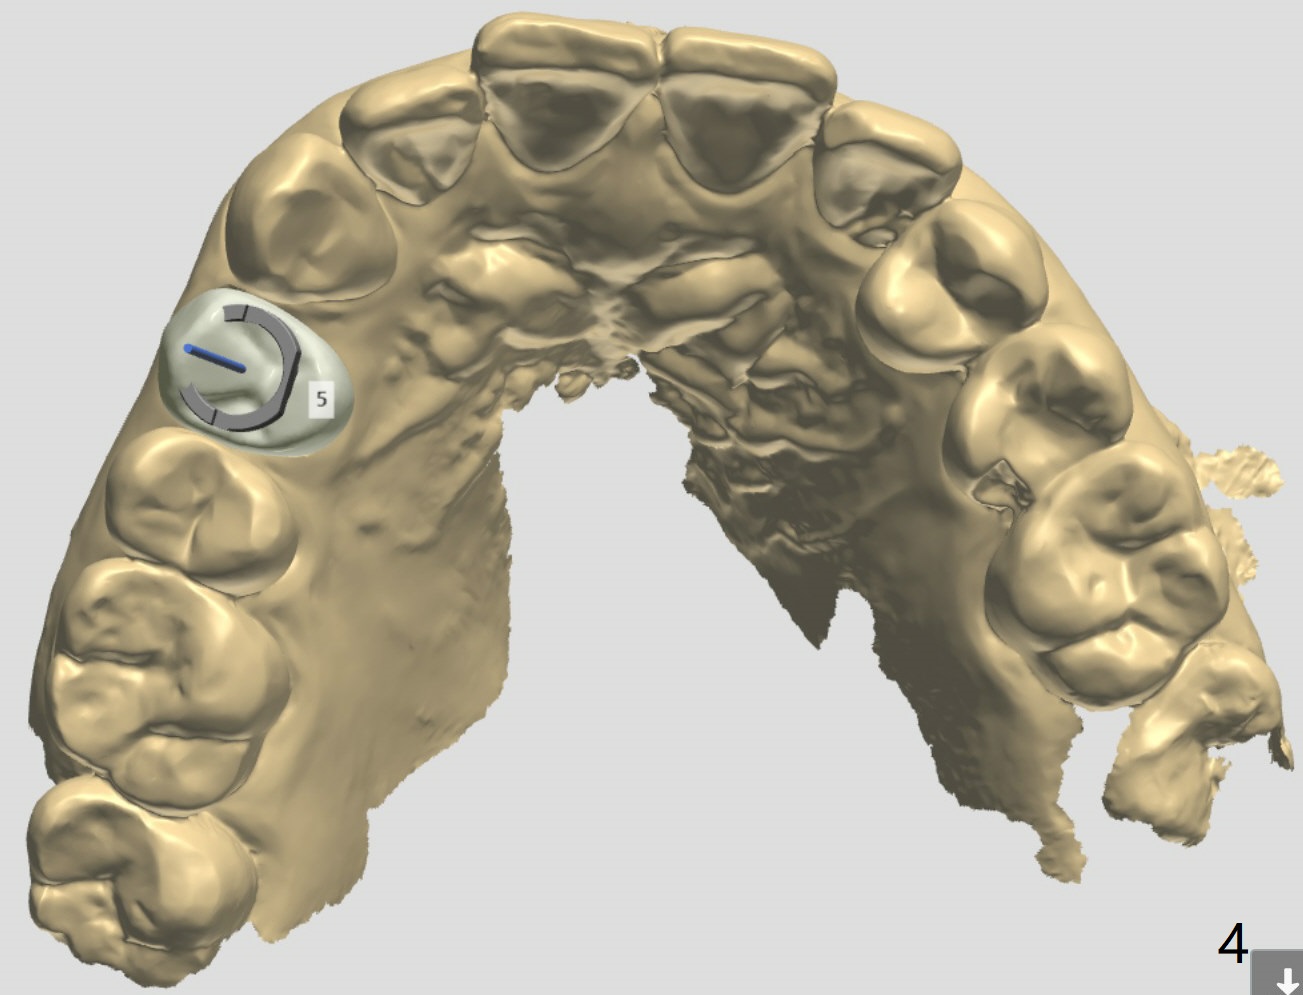

A 46-year-old woman

Xin Wei, DDS, PhD, MS 1st edition 06/28/2021, last revision 07/24/2021